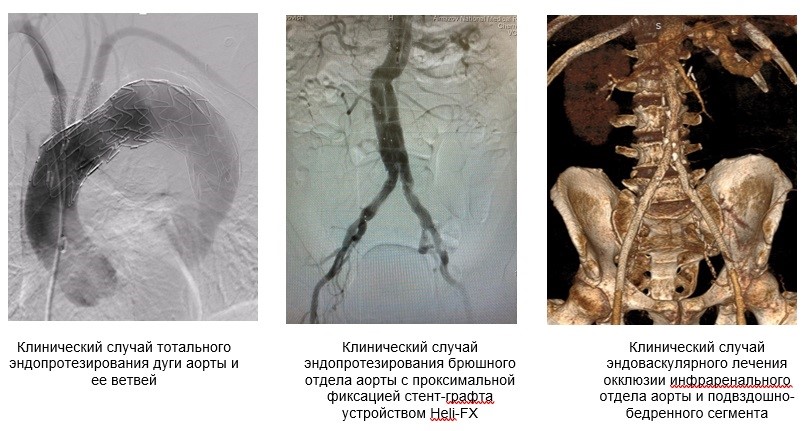

- Эндопротезирование дуги аорты с интраоперационной фенестрацией в стент-графте;

- Эндопротезирование торакоабдоминальной аорты фенестрированным/браншированным стент-графтом;

- Открытые и эндоваскулярные операции при заболеваниях брюшной аорты;